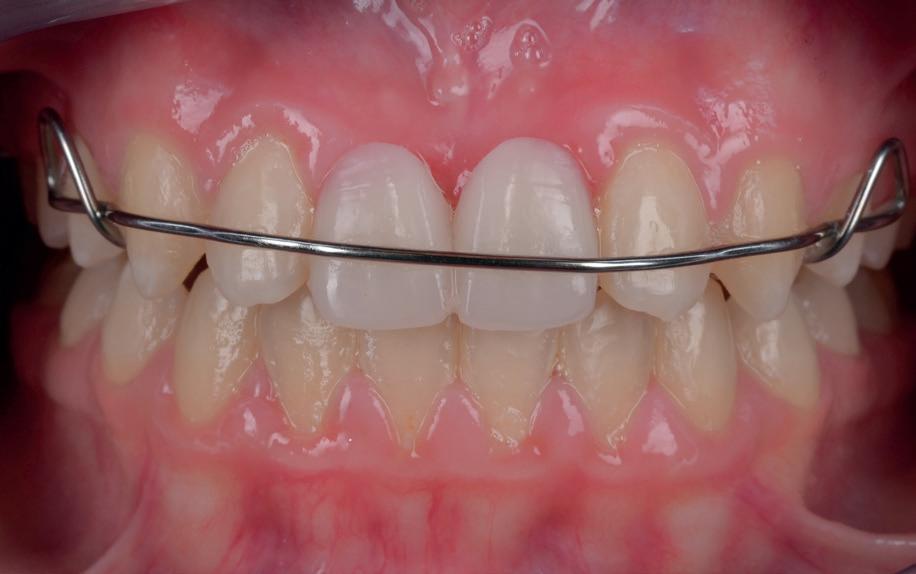

Op 16-jarige leeftijd werd de patiënt door haar behandelend orthodontist naar de auteur verwezen voor een restauratieve oplossing voor de afwezige 11 en 21. In de tussenliggende periode had patiënt een retainer gedragen met twee kunststof tanden (afbeelding 1). Zowel de patiënt als haar moeder hadden een sterke voorkeur voor een implantaat gedragen vaste oplossing. Gezien haar jonge leeftijd was dit echter nog geen optie, omdat er nog verticale groei te verwachten viel. Implanteren op jonge leeftijd – dat wil zeggen vóór het 21e levensjaar – kan resulteren in een infrapositie van het implantaat, omdat de rest van het gebit nog verticaal kan doorgroeien.

1. Retainer met twee frontelementen